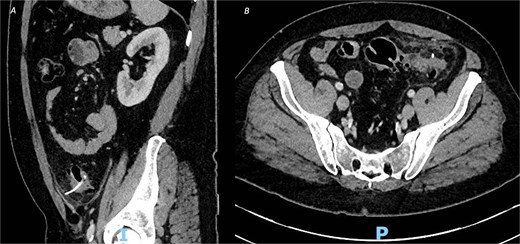

An urgent contrast-enhanced computed tomography (CT) abdomen–pelvis was performed, which revealed a 3.7-cm linear hyperdense foreign body, consistent with a fish or chicken bone, penetrating the wall of the sigmoid colon with associated surrounding pericolic fat stranding and small amount of localized pericolic air denoting small perforation (Fig. 1); there was no evidence of abscess formation, or distant free air.

CT of the abdomen and pelvic with contrast, demonstrating an ingested foreign body with localized perforation and pericolic inflammatory changes, in both (A) sagittal view and (B) axial view.